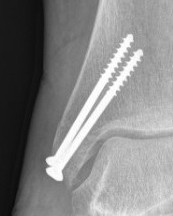

![]() |

| Type C: transverse fractures |

Type B: too small for two screws |

Screw fixation

AO surgery reference medial malleolus lag screws